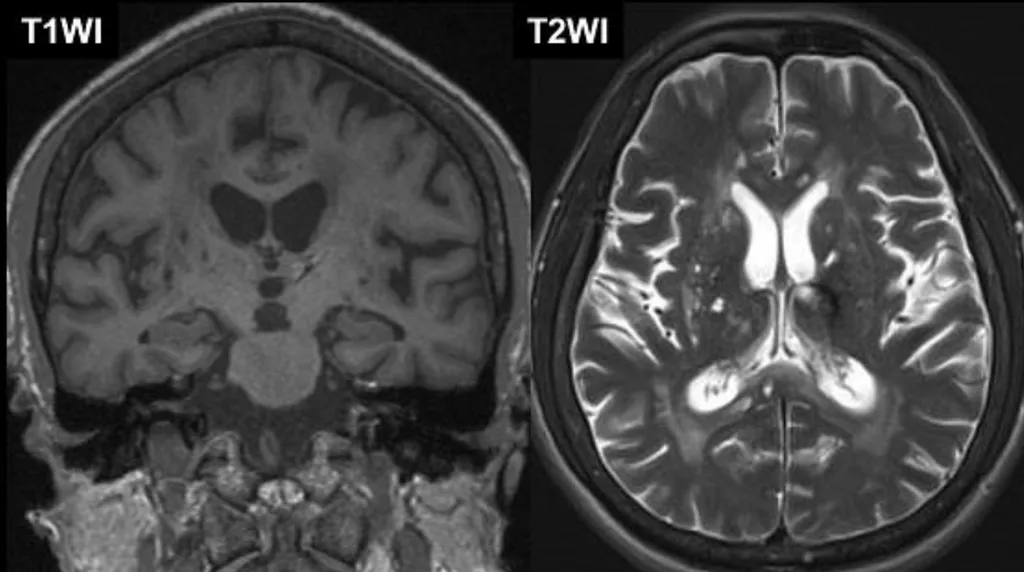

這張頭部磁振造影(MRI)的T2加權影像顯示大範圍的白質高訊號病灶,這些是血管性失智症的典型影像學特徵。